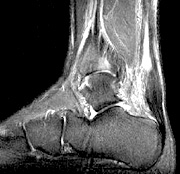

- Copyright – Stock Photo / Register Mark Sagittal T2 With Fat Saturation Fluoroquinolone antimicrobial drugs are used to treat an extensive range of bacterial infections including pneumonia, bronchitis, skin and urinary tract infections. They are marketed under numerous names; Ciprofloxacin, Cipro, Baycip, Cetraxal, Ciflox, Cifran, Ciplox, Cyprobay and Quintor are the most common. One needs to be a pharmacist to know all the different ways this drug is marketed.

The following is a case history:  A 55-year-old long-distance runner who is a regular chiropractic patient has a main complaint of right SI joint pain that is intermittent and aggravated by long periods of standing, walking or running. He had this problem before and generally only needs a couple of adjustments to relieve his symptoms. He also had some minor, bilateral calf pain with minimal tenderness in both Achilles tendons, which he stated was not uncommon when he was training to run in a marathon. Unfortunately, he failed to mention that three weeks previously, he had suffered a urinary tract infection and was given a 10-day course of Cipro. He was examined and given a chiropractic adjustment, with a recommendation to return in two days for another adjustment. He was also told to take it easy in terms of running for the next few days until his symptoms abated. He continued to run, with increasing symptoms mainly involving his right calf, with tenderness and swelling in the right Achilles tendon. He returned to his chiropractor, who immediately sent him for an MRI of his right Achilles tendon. The MRI demonstrated a partial tear of the tendon.